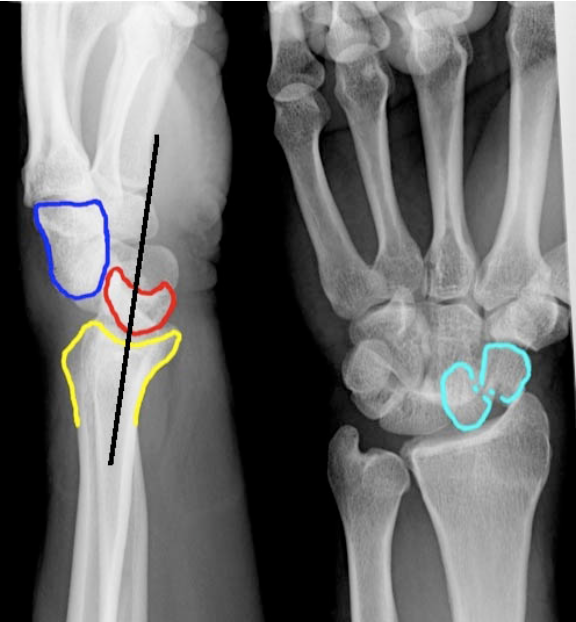

Perilunate dislocation

A

Mech: fall onto hyperextended hand

The four stages of ligamentous injuries in the

wrist are:

* stage I: scapholunate dissociation (less force)

* stage II: perilunate dislocation

* stage III: perilunate dislocation with associated

dislocation/fracture of triquetrum

* stage IV: lunate dislocation.

Xray:

Lateral view - Capitate disloation -> displaced dorsal to lunate

Lunate retains its normal contact with radius

PA view

Capitolunate joint space is obliterated and proximal and distal carpal rows overlap

Clinical:

Wrist swelling and tenderness but gross deformity absent

Mx

Ortho referral for arthroscopy reduction or ORIF

23

Q

Lunate dislocation

Lateral view

Lunate is pushed off the radius into the palm (“spilled teacup” sign)

Lunate has triangular shape (“

piece-of-pie sign

”)